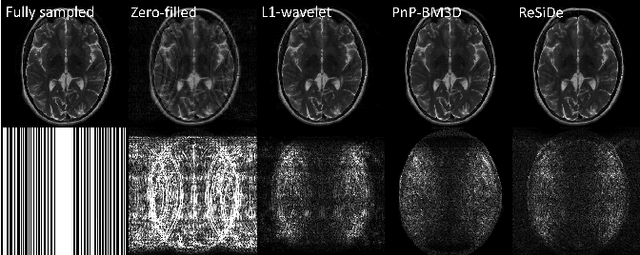

Plug-and-play (PnP) methods that employ application-specific denoisers have been proposed to solve inverse problems, including MRI reconstruction. However, training application-specific denoisers is not feasible for many applications due to the lack of training data. In this work, we propose a PnP-inspired recovery method that does not require data beyond the single, incomplete set of measurements. The proposed method, called recovery with a self-calibrated denoiser (ReSiDe), trains the denoiser from the patches of the image being recovered. The denoiser training and a call to the denoising subroutine are performed in each iteration of a PnP algorithm, leading to a progressive refinement of the reconstructed image. For validation, we compare ReSiDe with a compressed sensing-based method and a PnP method with BM3D denoising using single-coil MRI brain data.